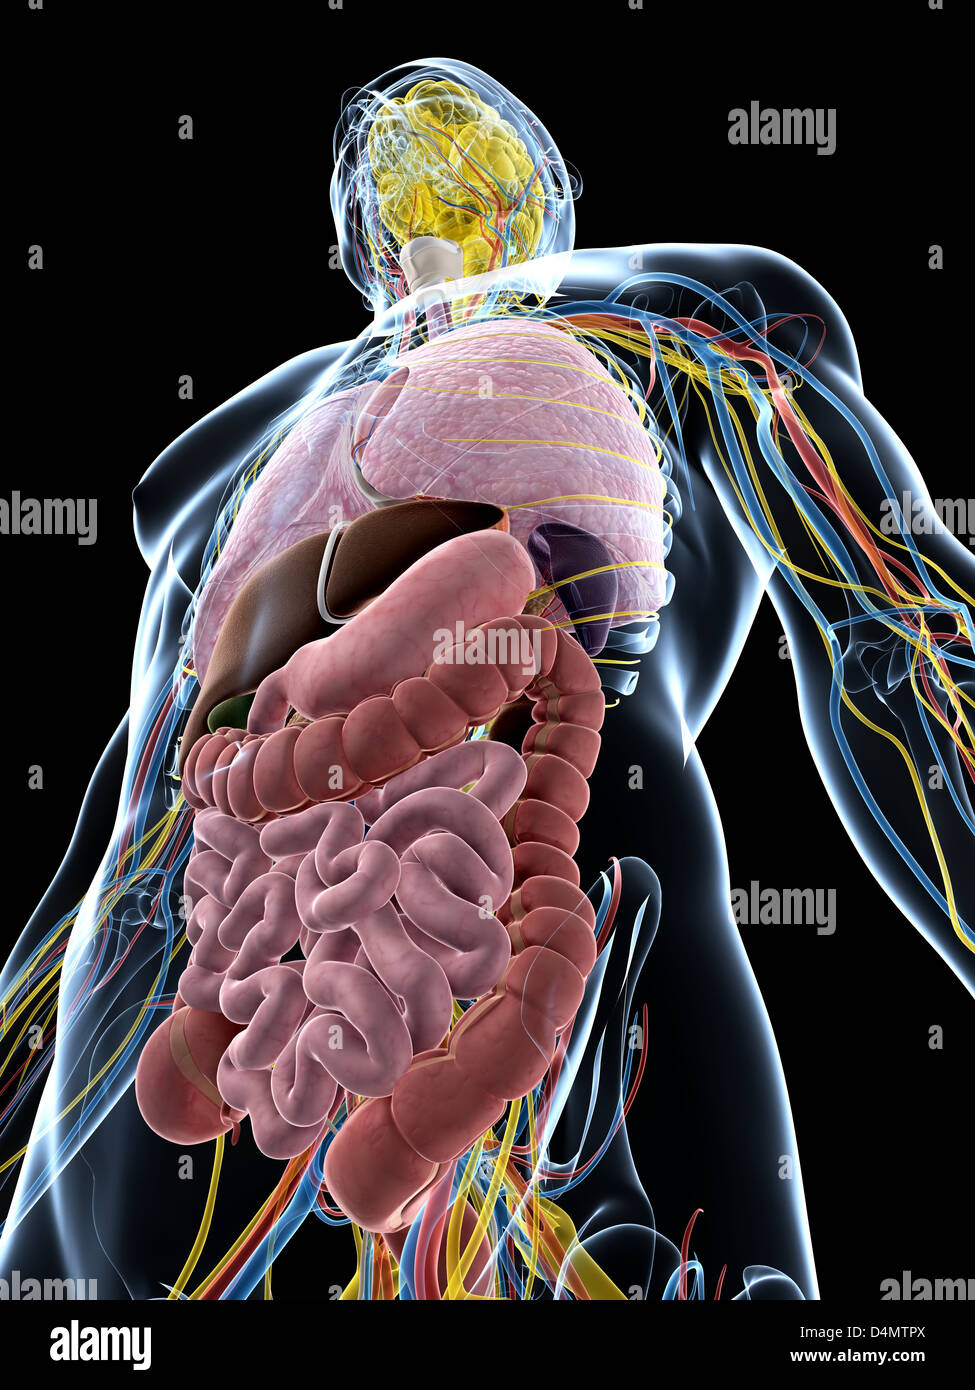

RFDGYRD7–Männliche Anatomie, inneren Organe allein, volle Atmungs- und Verdauungssystem, mit einigen Organen Cutaway. Anatomie-Bild.